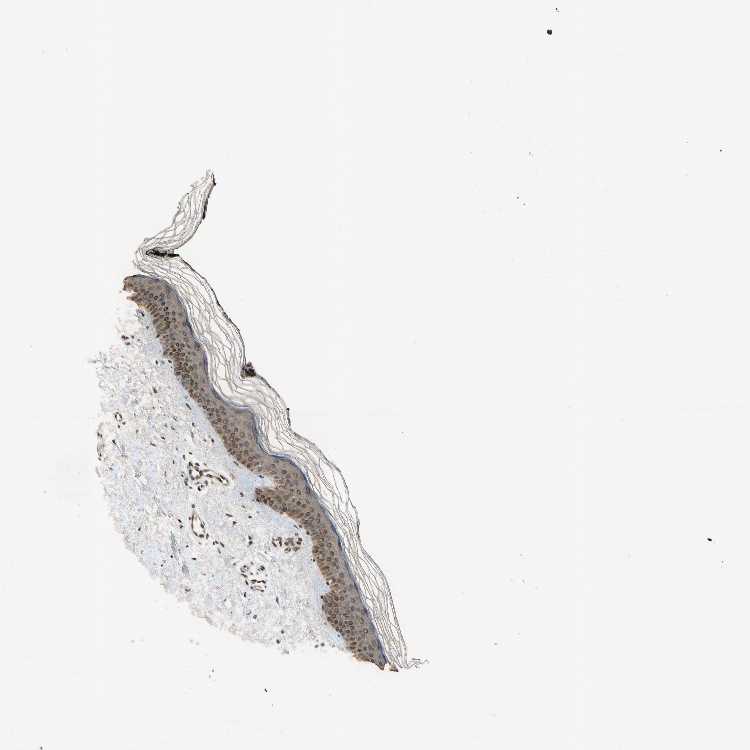

SKIN 2 - Antibody stainingi

Antibody staining in the annotated cell types in the current human tissue is reported as not detected, low, medium, or high, based on conventional immunohistochemistry profiling in selected tissues. This score is based on the combination of the staining intensity and fraction of stained cells.

Each image is clickable and will lead to virtual microscopy that enables deeper exploration of all samples and also displays staining intensity scores, fraction scores and subcellular localization as well as patient and tissue information for each sample.

Antibody CAB009860

Epidermal cells Low